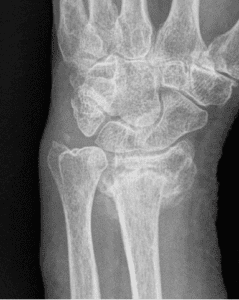

«It’s Only a Wrist Sprain» Often Understates Actual Injury

MIAMI, Sept. 20, 2021 /PRNewswire via COMTEX/ — MIAMI, Sept. 20, 2021 /PRNewswire-PRWeb – That self-diagnosed «only a wrist sprain» could well prove to be an injury in need of surgical repair, according to Miami-based orthopedist Alejandro Badia, who says ligament and cartilage damage or fractures of one or more of the wrist’s small bones… [Read More]